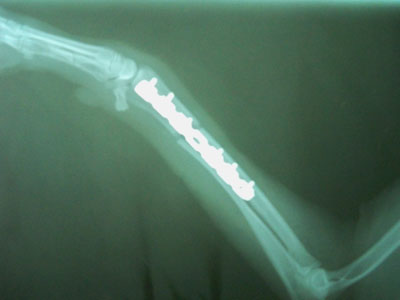

Mετά την ανάταξη του κατάγματος τοποθετήθηκε μεταλλική πλάκα 2mm στην πρόσθια επιφάνεια της κερκίδας με 3 κοχλίες στο κεντρικό και 3 κοχλίες στο περιφερικό τμήμα.Συρραφή του μυ΄ι΄κού τοιχώματος έγινε με interlocking ραφή και του δέρματος με π ραφές.

Μετεγχειρητικά χορηγήθηκαν 1 χάπι clindavet 150mg BID, ½ χάπι cefaseptin ΒΙD, 1,5ml BAYTRIL BID για 8 ημέρες.

Πριν επιστρέψει στους ιδιοκτήτες της τοποθετήθηκε νάρθηκας ο οποίος συστήθηκε να παραμείνει για 2 εβδομάδες και της χορηγήθηκε για τις επόμενες 8 ημέρες ANTIROBE 150mg SID, IMIZOL 0,8 ml και VIBRAMYCIN 1,5 χάπι SID γιατί διαπιστώθηκε πως είχε και ερλιχίωση.